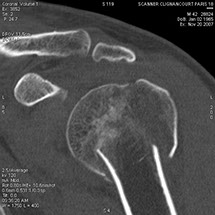

Cet appareil permet de faire des images en coupe du corps humain

et de les reconstruire dans différents plans pour mieux visualiser

Le scanner comporte un lit d'examen, sur lequel le patient est allongé, qui va se déplacer lentement pendant l’examen et un anneau qui va tourner autour du patient en émettant des rayons X (il contient le tube à rayons X et les récepteurs). Les rayons X vont traverser la région à étudier et permettre d’obtenir des images en coupe de la zone à étudier. Des traitements de numérisation informatique permettront d'obtenir  des images 2D ou 3D dans différents plans et volumes.

On peut faire ressortir le contraste de certains tissus, en particulier des vaisseaux sanguins, en injectant un produit dit "de contraste" (contenant de l'iode) qui a la propriété de fortement absorber les rayons X et donc de rendre très visibles les tissus où ce produit est présent (qui apparaissent alors hyperdenses, c'est à dire plus "blancs" sur l'image).

Grâce aux scanners multidétecteurs (ou multi-barrettes) à acquisition spiralée, on obtient une exploration très précise d'un large volume du corps humain pour un temps d'acquisition de quelques dizaines de secondes.